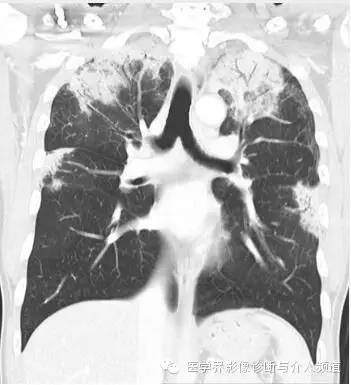

初始CT

初始胸片示两肺野多灶性斑片影,其中两肺上野靠近外周可见边界欠清的实变影,这是典型的慢性嗜酸性粒细胞性肺炎“肺水肿反转影”的表现。CT示两肺叶多灶性非节段性实变影,病变以两上肺周围性分布为主。

CEP的典型影像学表现:普通X线平片为非节段性、分布广泛互相融合的肺泡及间质性实变,病变以中上肺周围性分布为主,表现为“肺水肿反转影”。CT或HRCT表现为一侧或两侧融合性实变、斑片状实变、磨玻璃影、条带状致密影,实变灶与正常肺组织的分界截然清楚。此种典型征象并非见于所有CEP病例。